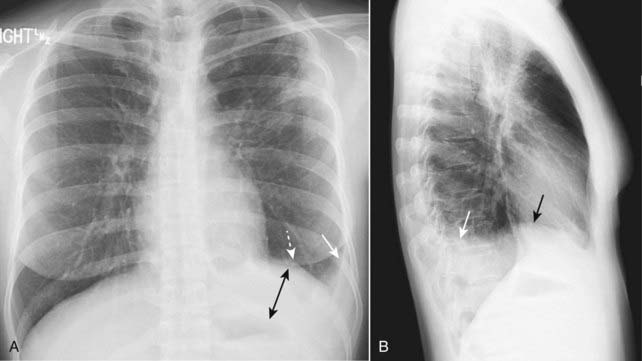

Figure 6-2 Right-sided subpulmonic effusion.

In the frontal projection (A), the apparent right hemidiaphragm appears to be elevated (solid black arrow). This edge does not represent the actual right hemidiaphragm, which has been rendered invisible by the pleural fluid that has accumulated above it, but the interface between the effusion and the base of the lung (thus the term “apparent hemidiaphragm”). There is blunting of the right costophrenic sulcus (solid white arrow). On the lateral projection (B), there is blunting of the posterior costophrenic sulcus (solid white arrow). The apparent hemidiaphragm is rounded posteriorly but then changes its contour as the effusion interfaces with the major fissure on the left side (solid black arrow).

Figure 6-3 Left-sided subpulmonic effusion.

In the frontal projection (A), more than 1 cm distance is seen between the air in the stomach and the apparent left hemidiaphragm (double black arrow). The edge between the aerated lung and the dotted white arrow does not represent the actual left hemidiaphragm, which has been rendered invisible by the pleural fluid that has accumulated above it, but the interface between the effusion and the base of the lung. There is blunting of the left costophrenic sulcus (solid white arrow) on both projections. On the lateral projection (B), the apparent hemidiaphragm is rounded posteriorly but then changes its contour as the effusion interfaces with the major fissure (solid black arrow).